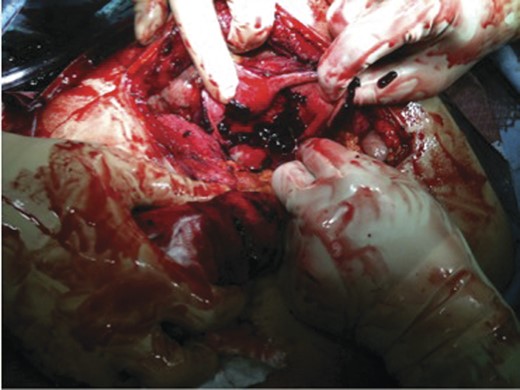

In the operating room a right Kocher incision was performed. Upon entering the peritoneal cavity a large haematoma was encountered with some old blood. Following the evacuation of the haematoma, the gallbladder was identified; it was massively distended with a haemorrhagic-appearing wall and had a tear in the fundus. Inside the gallbladder lumen clots and fresh blood was seen (Figs 3 and 4). It was clear that the bleeding cystic artery branch distended the gallbladder with blood leading to gallbladder rupture and free haemorrhage into the peritoneal cavity, with a total amount of evacuated haematoma of 2.5 L. A cholecystectomy was performed in a retrograde fashion, and a drain inserted before the closure of the abdomen. The patient was extubated and transferred to the recovery room in a stable condition. He did well post-operatively and was discharged home on the 6th post-operative day.

Pathology revealed an acute on chronic cholecystitis with a haematoma in the gallbladder wall (Fig. 5). The embolization material was identified in the small vessels leading to the gallbladder wall haematoma.